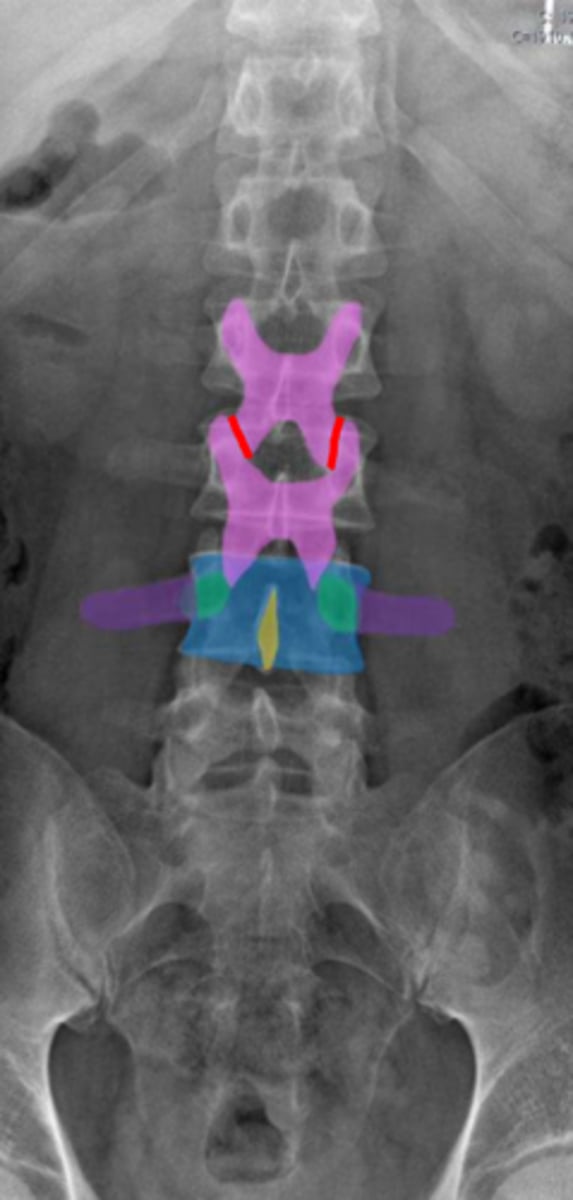

pedicles

Identify the green structure

spondylolysis

pars interarticularis

oblique view

What condition is being examined for in this radiograph?

What structure is it looking for?

What view is this radiograph in?